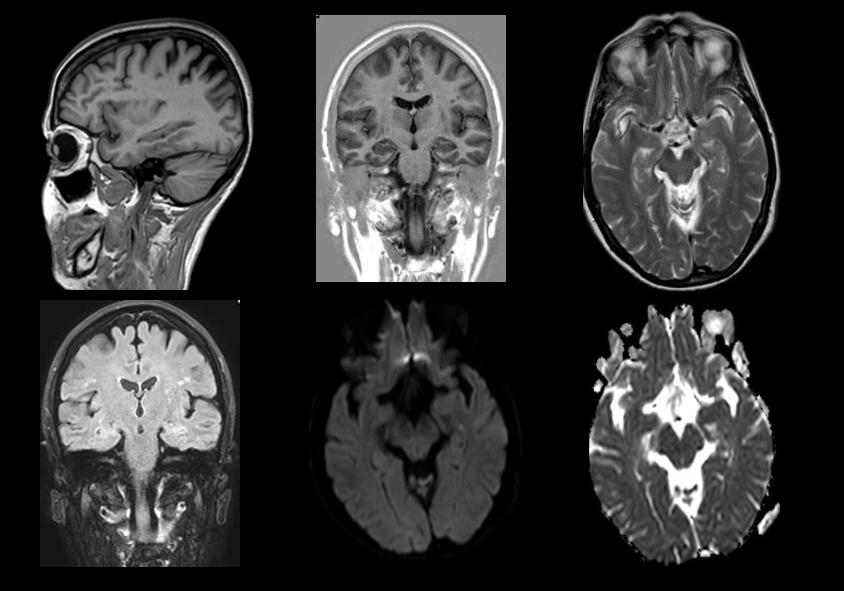

Secuencias de RM sin contraste intravenoso. En difusión se aprecia un foco de restricción puntiforme en hipocampo, que no se manifiesta en otras secuencias.

Lesiones puntiformes en secuencia de difusión en el contexto de amnesia global transitoria.